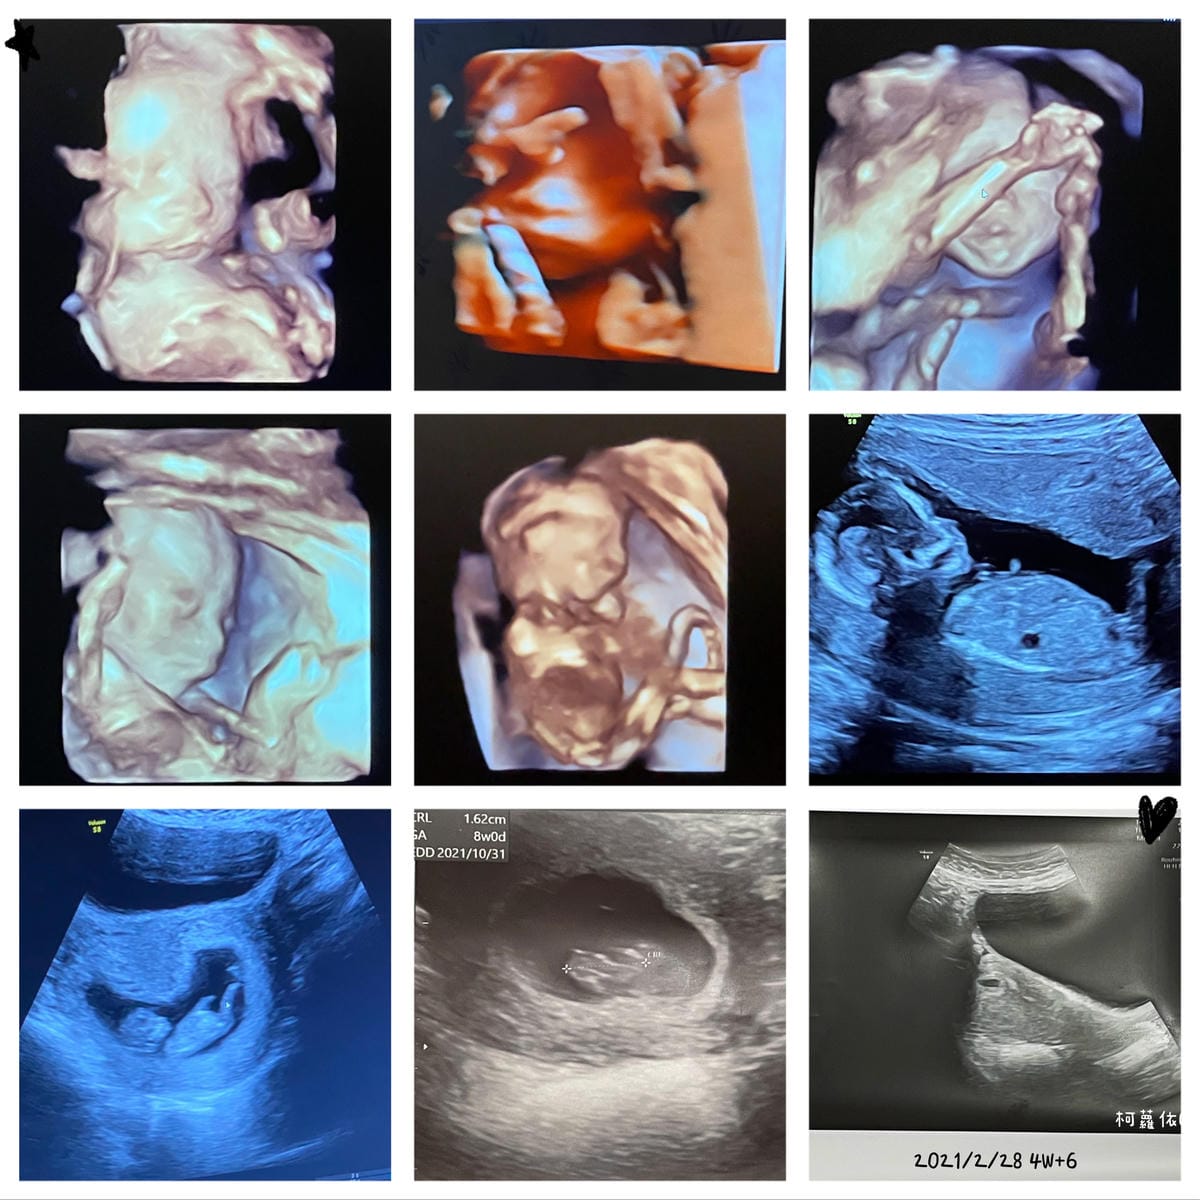

時間真的過很快,還記得一開始是一個小點點,然後開始慢慢藉由產品照超音波看出可愛的輪廓